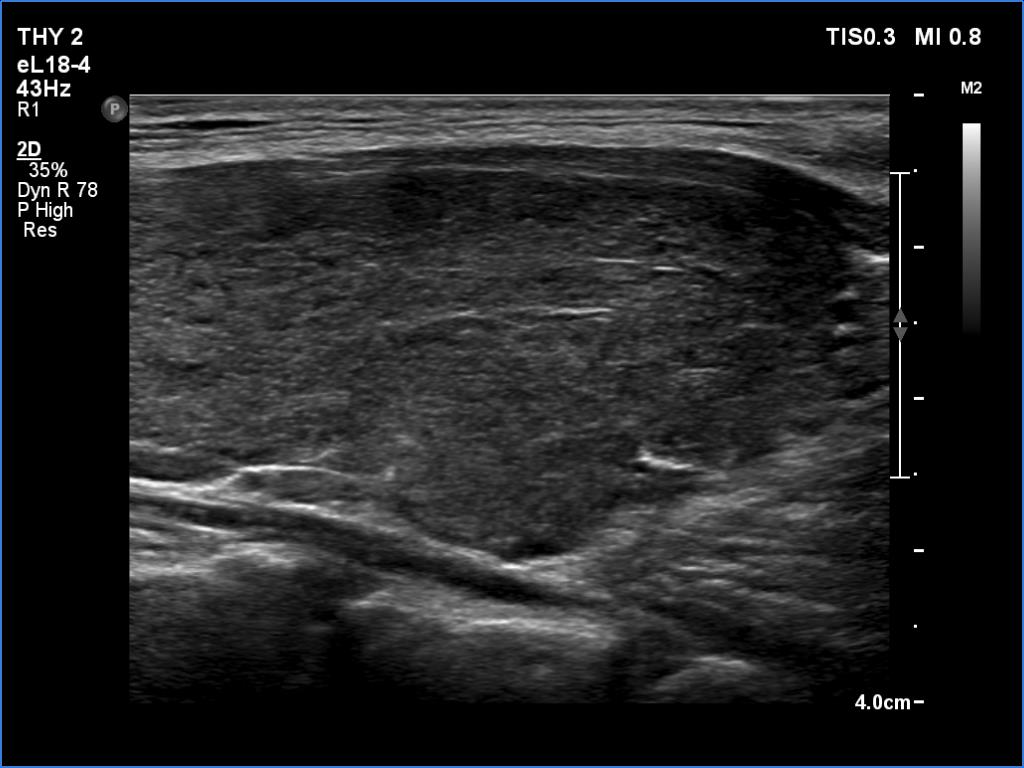

Graves' disease - case 121 (ultrasonographic picture 7)

Lower part of the left lobe, longitudinal view.